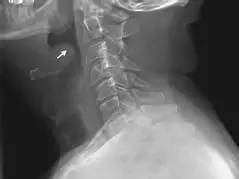

急性会厌炎致命的危险是喉梗阻。

急性会厌炎的治疗,应使用足量有效抗菌素和糖皮质激素(甲泼尼龙、地塞米松等),以迅速缓解会厌水肿导致的喉梗阻。对于药物治疗无效而出现喉梗阻症状者,要果断行气管切开,以免发生窒息而危及生命。如会厌脓肿已经形成,可在喉镜下切开排脓。